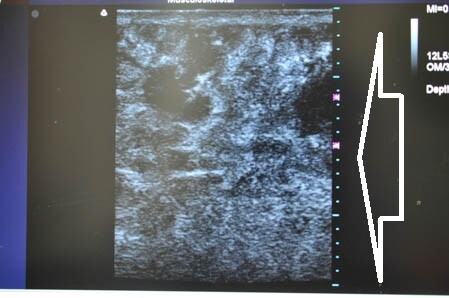

下腹部も同様に。

↓ ↓ ↓